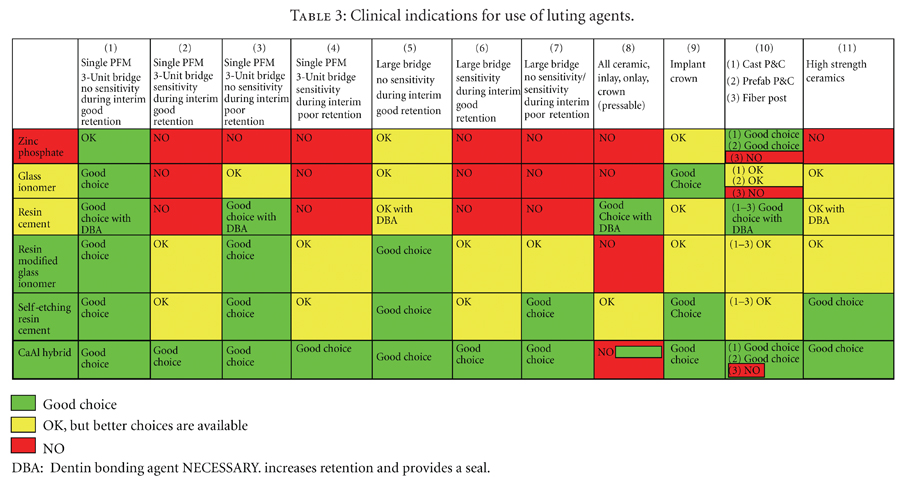

Mrs. Jones and her husband presented to my Prosthodontic Specialty clinic for an additional opinion regarding her treatment options to improve her existing oral condition. After conducting an interview with Mrs. Jones and completing a comprehensive clinical examination, along with diagnostic records, I presented three potential treatment plans. The advantages and disadvantages, risks and benefits … Read more